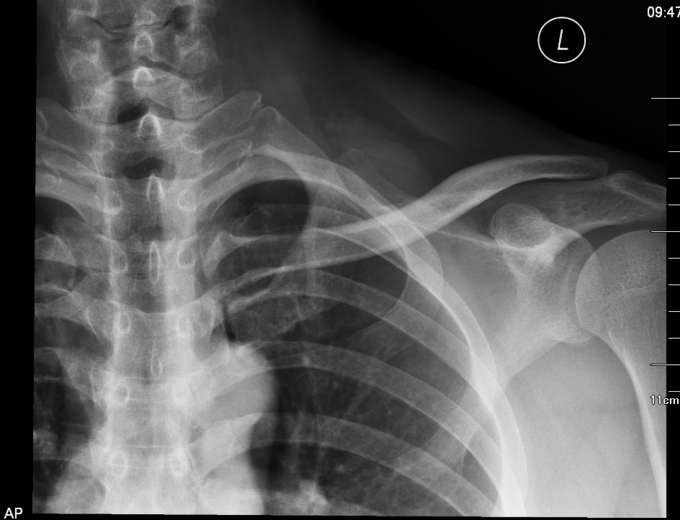

患者于2015年6月26日骑自行车摔伤时导致右肩部疼痛、活动障碍,意识状态可,被送至当地医院,行X线片检查示:右肩锁关节脱位,给予保守治疗。为求进一步治疗来我院,门诊行相关检查后,门诊以“右肩锁关节脱位”为诊断收住入院。

右肩外侧局部肿胀, 可见5x10cm不规整瘀斑,脱位锁骨远端端隆起于皮下,压痛不明显,未触及骨擦音及骨擦感,按压时有兵乓球感,右肩关节外展受限,手指活动灵活,锁骨下区及三角肌区皮肤痛觉无减退,桡动脉搏动有力,末梢血运良

诊断:右肩锁关节脱位 入院后完善检查,完善心电图,生化检查后。局部消肿后,查无手术禁忌症后行右肩关节脱位锁骨钩钢板内固定术